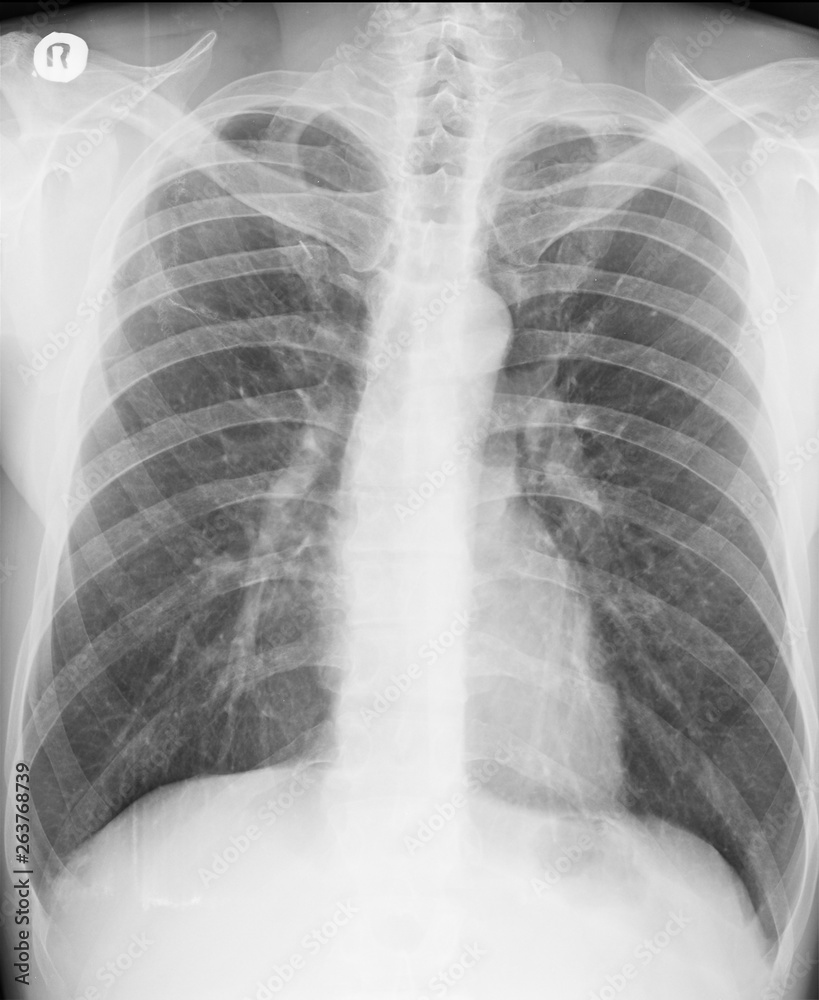

From stock.adobe.com

Chest Xray. PA view. Lung fields with persistent pulmonary opacities Lung Field Lucency  Decreased lung density on images can be described as pulmonary hyperlucency on conventional chest radiographs and. This relative overaeration may be due to subnormal blood perfusion,. The purpose of this review is to provide a practical diagnostic algorithmic approach to pulmonary hyperlucencies incorporating clinical history. Thin body habitus and poliomyelitis are important causes of hyperlucent lung fields in developing countries.. Lung Field Lucency.